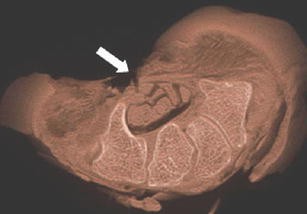

Flat-panel volume computed tomography (fpVCT) is a recent development in imaging. We discuss some of the musculoskeletal applications of a high-resolution flat-panel CT scanner. FpVCT has four main advantages over conventional multidetector computed tomography (MDCT): high-resolution imaging; volumetric coverage; dynamic imaging; omni-scanning. The overall effective dose of fpVCT is comparable to that of MDCT scanning. Although current fpVCT technology has higher spatial resolution, its contrast resolution is slightly lower than that of MDCT (5-10HU vs. 1-3HU respectively). We discuss the efficacy and potential utility of fpVCT in various applications related to musculoskeletal radiology and review some novel applications for pediatric bones, soft tissues, tumor perfusion, and imaging of tissue-engineered bone growth. We further discuss high-resolution CT and omni-scanning (combines fluoroscopic and tomographic imaging).